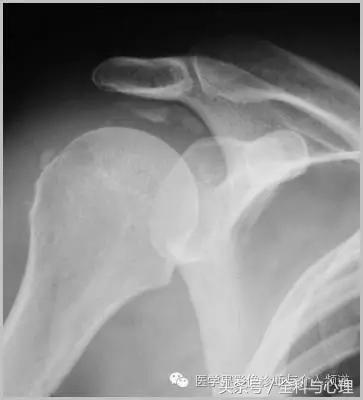

一、肿瘤样钙质沉着症

累及多个关节,范围较大,表现为多房囊状的高密度影。

原发性:罕见,多为家族性,多见于非洲裔美国人,钙磷正常。

继发性:多见于慢性肾功能不全患者。钙磷均有升高。

肿瘤样钙质沉着症